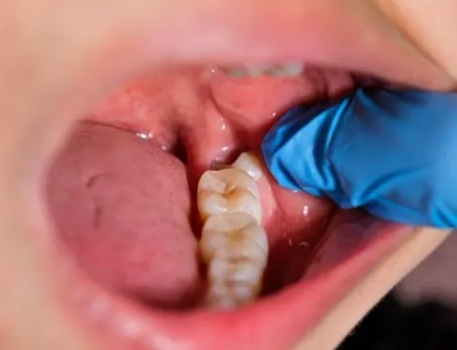

1. Impaction – When the wisdom tooth does not have enough space to emerge properly, it may become trapped in the gums or jawbone.

3. Gum Inflammation – The gum tissue surrounding a wisdom tooth can become swollen and painful.

Before / After